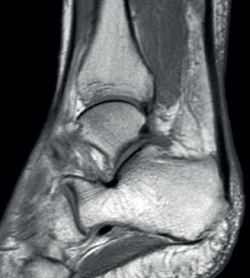

Figure 2. Retroachilleal bursitis.

However, in the chronic forms of insertional Achilles tendinopathy or enthesopathy (present in the distal 2 cm of the tendon), we can observe calcifications within the tendon in the form of traction enthesophytes or at the insertion site in the form of spurs. These conditions are often associated to alterations of the retroachilleal bursa(5,31)(Figure 2).

Retrocalcaneal bursitis is characterized by an increased volume of the bursa, with the possible association of Haglund deformity(25). In the case of retroachilles or superficial calcaneal bursitis we can identify fluid between the skin and the Achilles tendon(5).

Retrocalcaneal bursitis is in turn characterized by hyperintense images in T2 sequencing in the retrocalcaneal recess(5), while in retroachilles bursitis or superficial calcaneal bursitis, inflammation of the bursa results in hyperintense images in T2 sequencing(5).